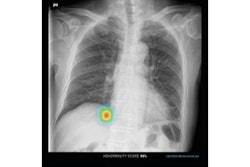

Tallam and colleagues conducted a study that included 8,992 patients who underwent colorectal cancer screening with CT colonography; of these, 572 had type 2 diabetes and 1,880 were dysglycemic. The researchers segmented images of the pancreas using a deep-learning algorithm that flagged biomarkers such as CT attenuation, volume, fat content, and the fractal dimension of the organ, as well as visceral fat and atherosclerotic plaque.

The deep-learning model showed that diabetics had lower pancreas CT attenuation and higher visceral fat than those patients who did not have the disease. Other key predictors of type 2 diabetes on CT included the following:

"Fully-automated CT biomarkers can be used for the opportunistic detection and prediction of type 2 diabetes on scans performed for other indications," Tallam and colleagues concluded.